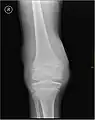

Hémarthrose

L'hémarthrose est un épanchement de sang dans une cavité articulaire consécutif d'une lésion ligamentaire, d'une fracture osseuse ou encore d'une atteinte du cartilage osseux[1]. Cette physiopathologie est caractéristique des personnes atteintes d'hémophilie sévère et dans une moindre mesure chez les formes modérées, car chez les hémophiles, l’absence ou l’altération d’un des facteurs de la coagulation (VIII ou IX selon le type d’hémophilie) perturbe le processus de la coagulation, au point qu’un traumatisme minime peut provoquer un saignement prolongé[2]

Près d'un quart des lésions sévères des ligaments et des genoux capsulaires entraînant une hémarthrose sont associées à des lésions cartilagineuses pouvant mener à une arthrite dégénérative progressive.